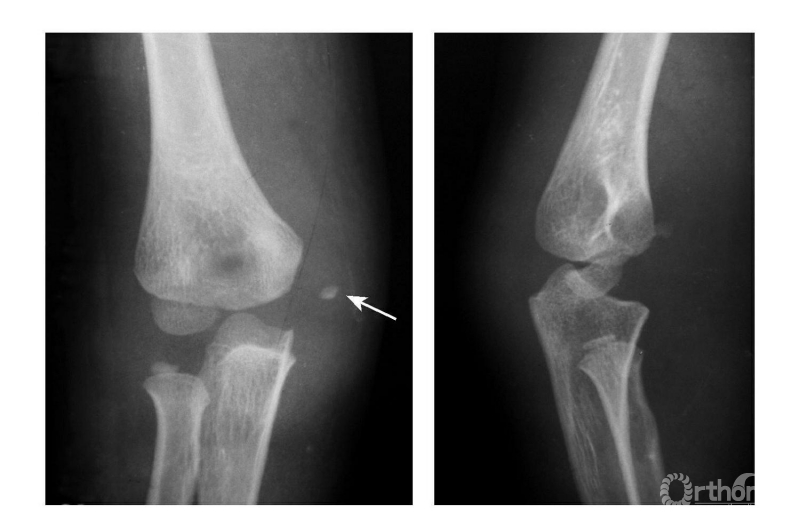

例1:内上髁骨骺撕脱并移至尺肱关节间(图6)。

图6

例2:内上髁撕脱骨折,骨块移至尺肱关节间(成人)(图7)。

图7